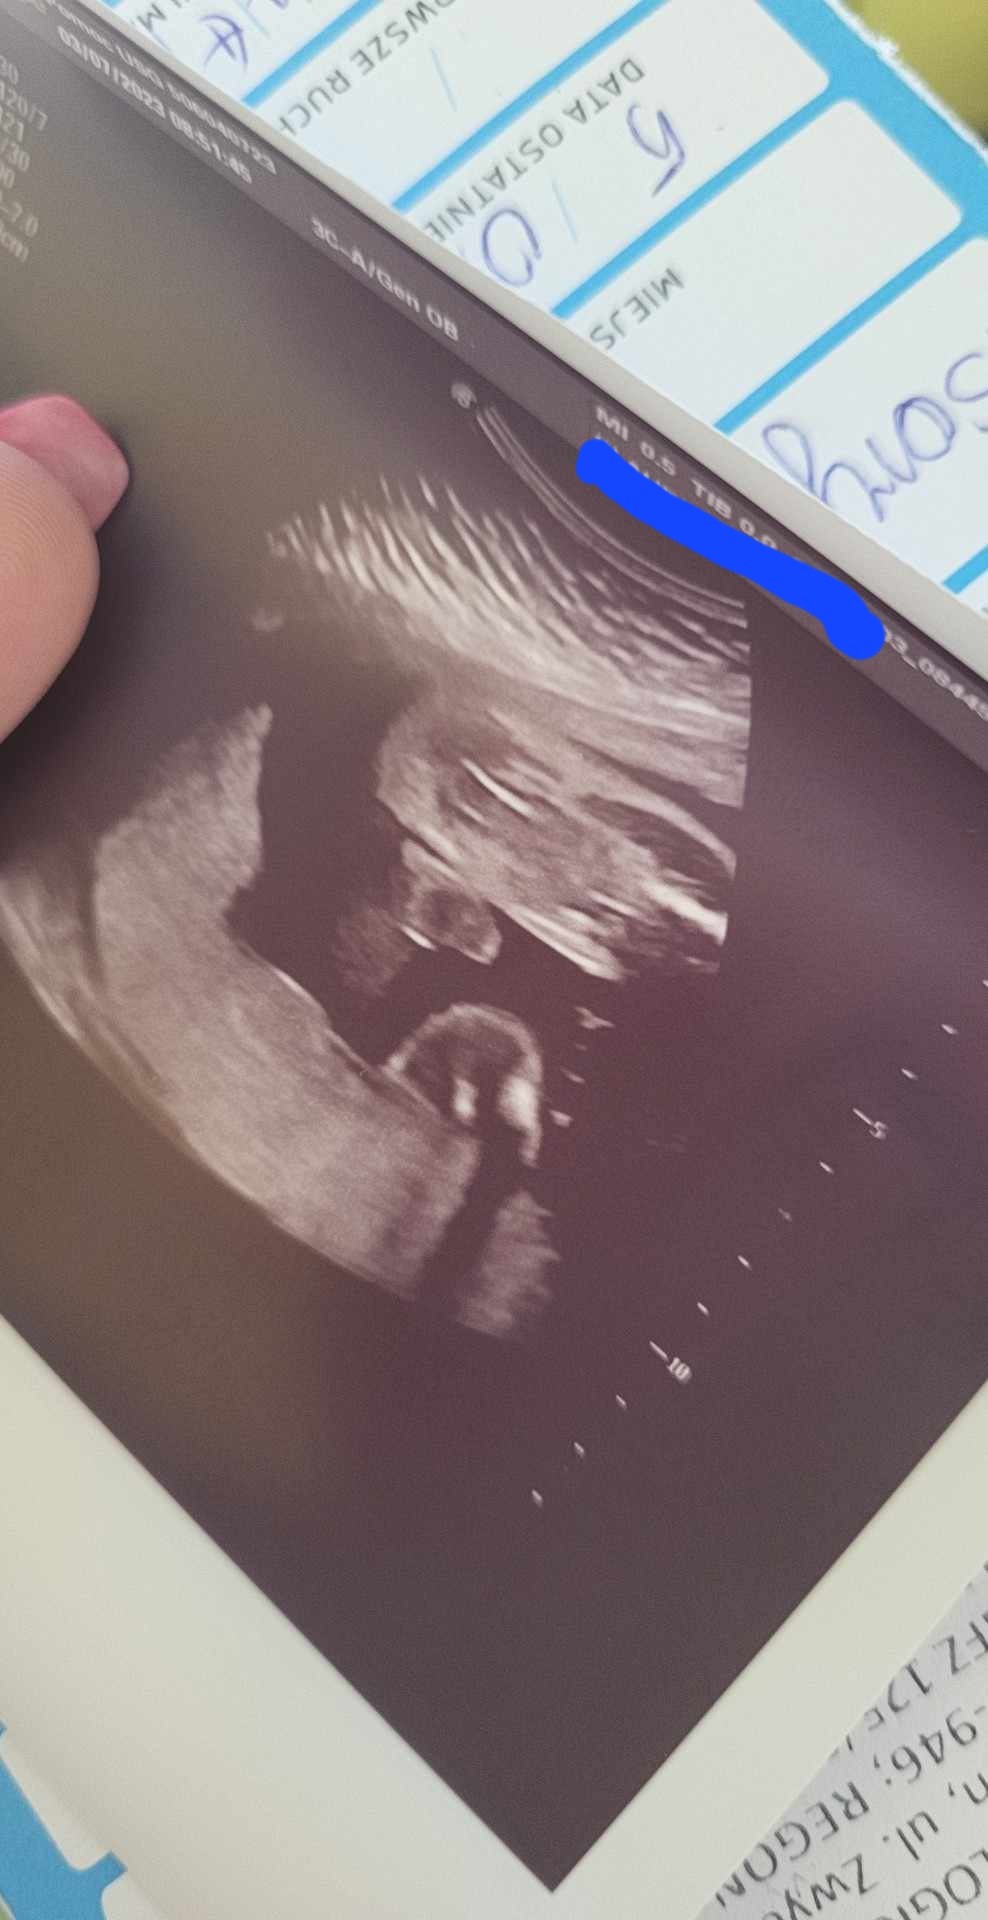

Dziękuję za odpowiedź :) a podesle jeszcze takie zdjecie : czyli możliwe zeby na tym to była pepowinka albo maleństwo cos podłożyło? :) Pani Doktor twierdzi, że w 24 tygodniu to powinny być już dobrze widoczne jajeczka a tu nie wygląda na to :)

Cześć dziewczyny! Dzisiaj jestem po usg, nawet moja Pani Doktor zaczęła mieć wątpliwości i powiedziała, że to chyba jednak chlopczyk! :) ale numer.. co usg inna płeć 🙈

Powiedziała tylko, że chlopczyk bo widzi jajeczka. Ja oczywiście nie widziałam nic jak to na każdym usg :) za tydzień mam 3 prenatalne mam nadzieję że wtedy lekarz bez wątpliwości powie co tam się kryje. Sama była zdziwiona, że tak wyszło tymbardziej że na poprzednim usg też dzieciątko było dobrze ułożone i nie widziała ani siusiaka ani jajeczek :)